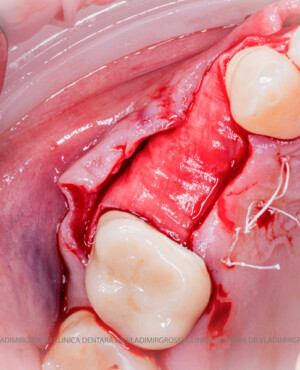

Un element esențial în procedura de aditie osoasă este utilizarea membranelor biologice, care izolează materialul osos de țesuturile moi (gingie) pe durata procesului de vindecare. Cele mai recomandate sunt membranele resorbabile din colagen sau pericard.

Procesul de refacere osoasă este complex, însă, simplificat, se bazează pe faptul că osul adăugat se integrează treptat, fiind înlocuit parțial cu os natural, oferind astfel suportul necesar implantului.

Aditia gingivală este o procedură chirurgicală ce corectează diverse probleme estetice și funcționale, cum ar fi recesiunea gingivală. În implantologia modernă, aditia de țesut moale este utilizată aproape în fiecare intervenție de inserție a implantului dentar pentru a asigura un aspect estetic natural și o bună integrare a implantului în cavitatea bucală.